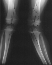

X-ray Set 2. 16 Months post Fracture, Right 8* Left 26* Mechanical axis, Left 34* Femoral Tibial Angle.

At this time the child was experiencing significant pain and inability to ambulate. He was treated with varus producing closing wedge osteotomy of the proximal tibia with neutral alignment